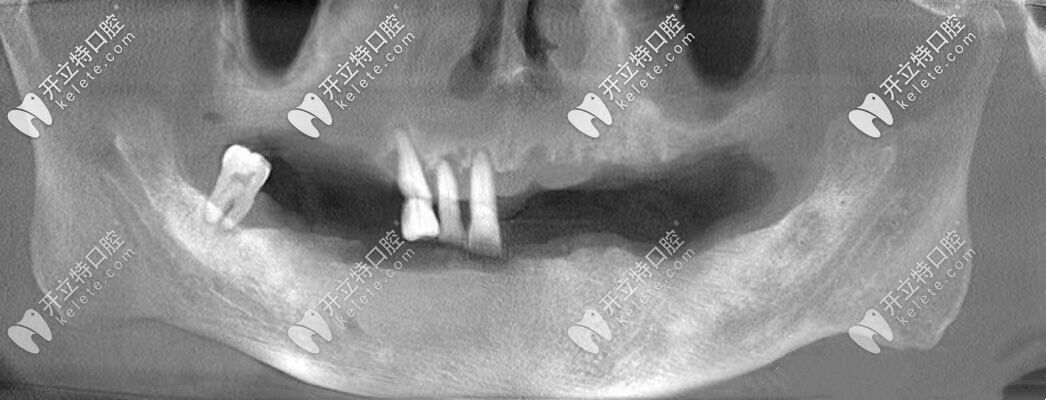

張叔牙齒的上頜僅剩3顆牙,下頜僅剩1顆牙,他之前一直戴的是活動假牙,但是當看著支持掛鉤的基牙一顆顆松動、齲壞到拔除,張叔的心里也是很難過的。

由于常年戴活動假牙,導(dǎo)致自身牙槽骨的條件較差,醫(yī)生給張叔設(shè)計了全口即刻種植牙的方案,沒想到3個小時左右的時間就完成了種植牙,并且真的是當天種牙,當天吃飯啊!